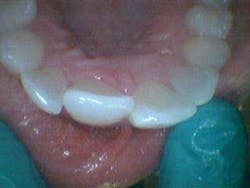

A healthy 7-year-old female presented directly from school with her father stating that she fell off the monkey bars. This was her first visit to the dentist. Initial exam revealed that tooth No. 8 was partially avulsed (Fig. 1) with only a slight attachment to the gingiva. All other teeth appeared clinically normal. Radiograph assessment revealed a large open apex on No. 8. The patient was given a local. The clot was removed and the area irrigated with a saline rinse. Next, the tooth was gently repositioned in the socket with slight compression of facial and lingual alveolar processes. A nonresilient wire splint was placed from NOs. 7 through 9. The patient was given an Rx of antibiotics for potential infection. A one-week assessment revealed a significant decrease of swelling with No. 8 appearing fairly stable. After eight weeks, tooth No. 8 had a slight delay to cold testing with all other teeth testing normal. The splint was removed. It was discussed with the father that the delayed response could be attributed to the healing of pulp or potential pathology. A two-month follow-up was recommended.